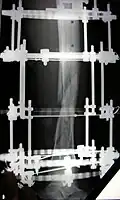

The photographs and radiographs illustrate the application and emplacement of an external fixator, an Ilizarov apparatus, to repair the open fracture of the lower left leg of a man. The photographs were taken four weeks after the patient fractured the shinbone (tibia) and the calfbone (fibula) of his left leg, and two weeks after the surgical emplacement of the Ilizarov apparatus to immobilise the leg and isolate the wound and fracture site to facilitate healing.

X-ray of the fracture site and the emplaced apparatus, two months post-fracture; perspective 1-4. -

X-ray of the fracture site and the emplaced apparatus, two months post-fracture; perspective 2-4. -

X-ray of the callus forming at the fracture site, three months post-fracture; perspective 3-4. -

X-ray of the callus forming around the fracture site, three months post-fracture; perspective 4-4. -

X-ray perspectives of the callus-formation progress and healing of the fractured tibia and fibula bones, four months post-fracture.